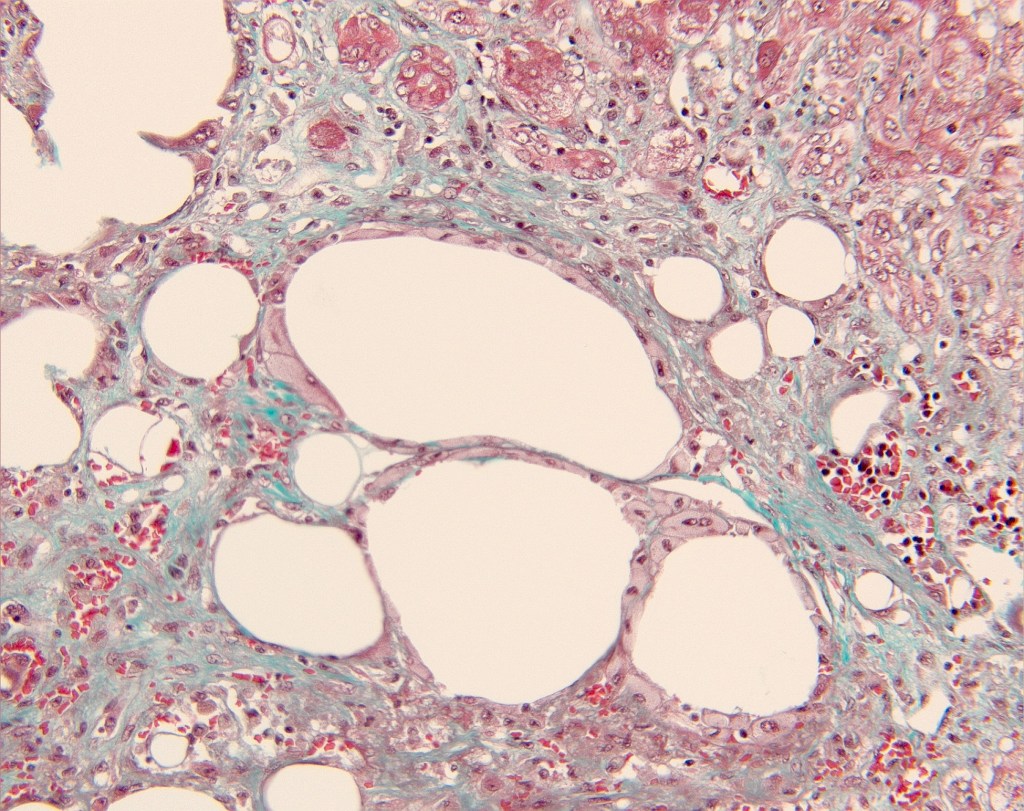

lipopeliosis